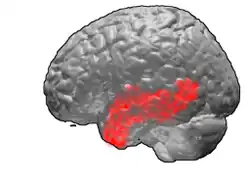

Brodmann area 21, or BA21, is part of the temporal cortex in the human brain. The region encompasses most of the lateral temporal cortex and is also known as middle temporal area 21. In the human it corresponds approximately to the middle temporal gyrus.

BA21 is a subdivision of the cytoarchitecturally defined temporal region of the cerebral cortex. BA21 is superior to BA20 and inferior to BA40 and BA41. It is bounded rostrally by the temporopolar area 38 (H), ventrally by the inferior temporal area 20, caudally by the occipitotemporal area 37 (H), and dorsally by the superior temporal area 22 (Brodmann-1909).